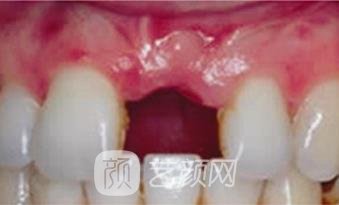

三、上海六院口腔科牙齿种植案例

小的时候没有刻意保护自己的牙齿,年龄超过40岁之后就发现了牙根松动的情况,有那么一两颗牙松动的比较厉害,干脆选择把牙齿拔掉做了种植,经过修复之后的牙齿,相对来说还是比较稳固的,用了有半年的时间进行恢复,已经没有不舒服的感觉。